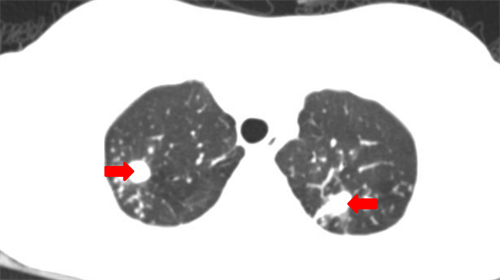

CT示小美(化名)双肺有多发病灶

据小美的母亲王女士介绍,小美于5个月前出现双下肢红斑,偶尔伴有瘙痒,带着孩子辗转市内多家医院就诊,考虑“结节性红斑”,给予激素类药物内服及外敷。小美病情刚开始有好转,但随后逐渐加重,反复出现下肢皮肤溃疡、坏死、流脓,双下肢还留下了褐色瘢痕、痂皮,并且体重明显下降,发热不退。王女士心急不已,带着小美辗转到了省级医院皮肤科就诊,经过一系列检查后发现小美的皮肤问题只是冰山一角,肺部也有多发病灶,考虑结核可能性大,为了得到更规范的诊治,小美转入91短视频 学生儿童结核科接受住院治疗。

刚入院时,小美高热,双下肢皮肤溃烂、水肿、营养差,学生儿童结核科主任周海依迅速组织皮肤科、肺外结核科、病理科、呼吸科、感染科、营养科等多学科会诊。医生为小美进行了皮肤活检,确诊其患有皮肤结核,随即迅速为她制定了个性化的治疗方案,每天对皮肤创面进行清创及换药。